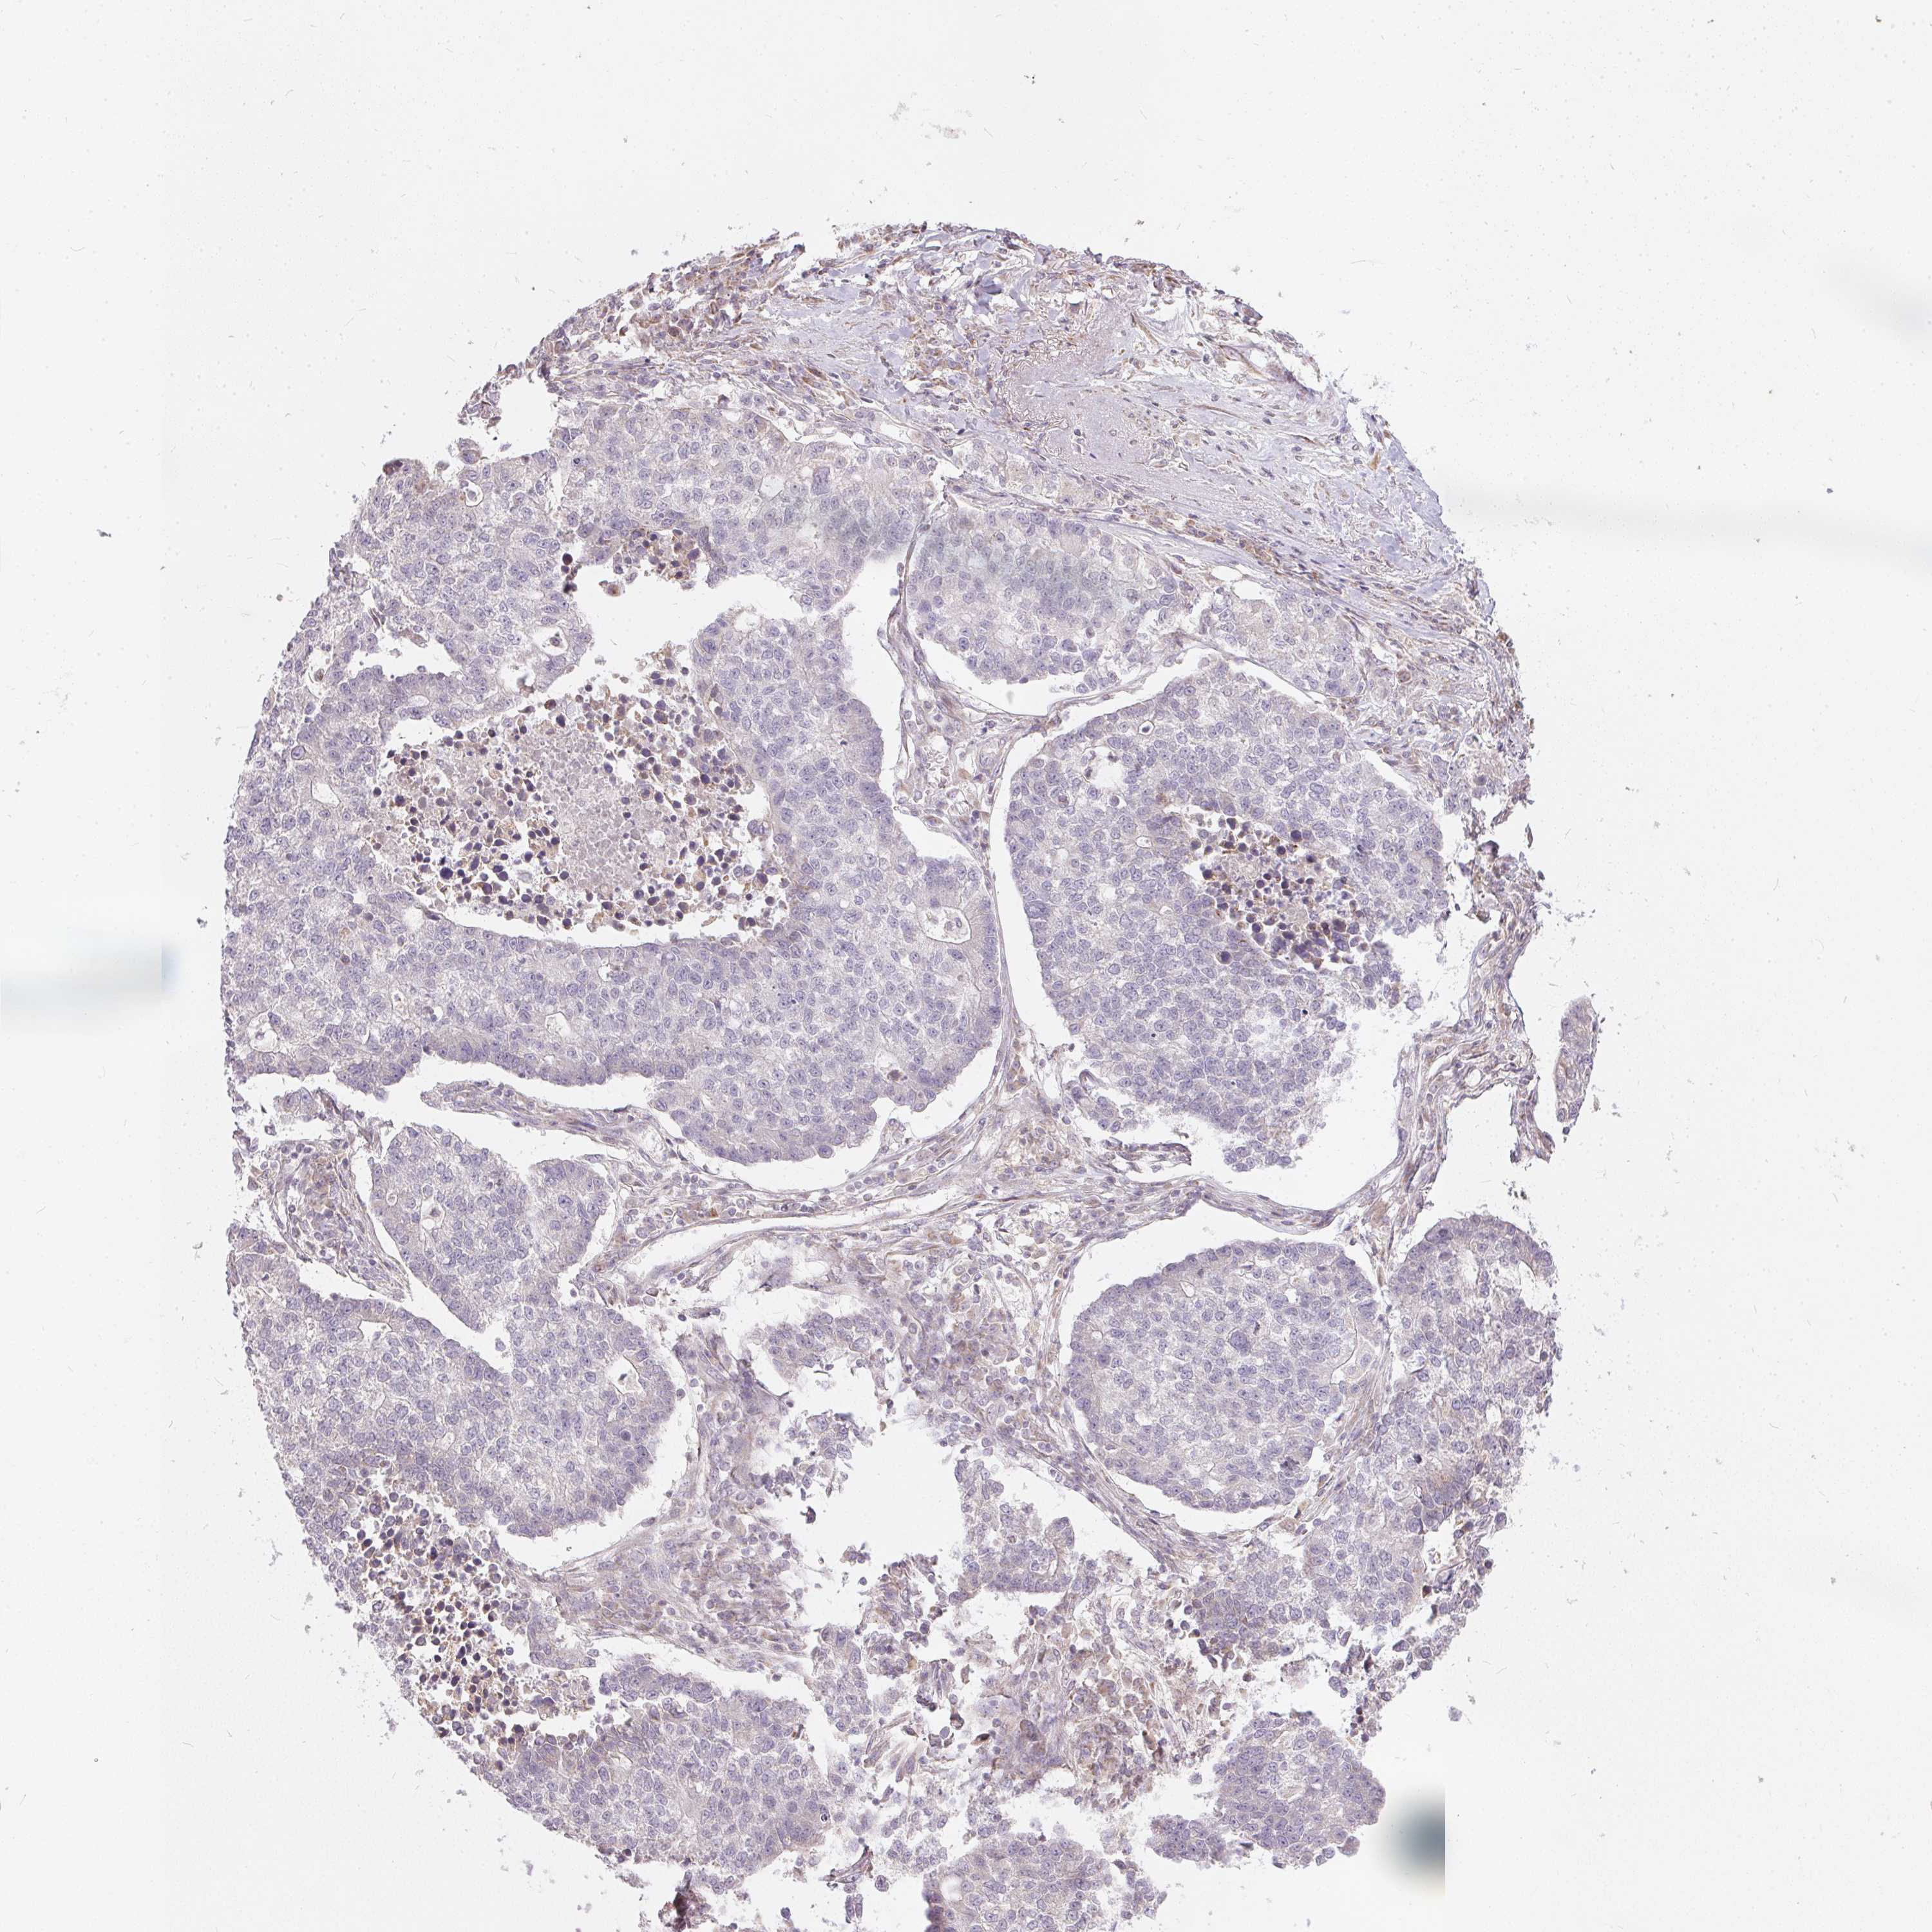

LUNG ADENOCARCINOMA (VALIDATION) - Interactive survival scatter ploti

The Survival Scatter plot shows the clinical status (i.e. dead or alive) for all individuals in the patient cohort, based on the same data that underlies the corresponding Kaplan-Meier plots. Patients that are alive at last time for follow-up are shown in blue and patients who have died during the study are shown in red.

The x-axis shows the expression levels (FPKM) of the investigated gene in the tumor tissue at the time of diagnosis. The y-axis shows the follow-up time after diagnosis (years). Both axes are complimented with kernel density curves demonstrating the data density over the axes. The top density plot shows the expression levels (FPKM) distribution among dead (red) and alive patients (blue). The right density plot shows the data density of the survived years of dead patients with high and low expression levels respectively, stratified using the cutoff indicated by the vertical dashed line through the Survival Scatter plot. This cutoff is automatically defined based on the FPKM cutoff that minimizes the p-score. The cutoff can be changed by dragging the vertical line or by entering a cutoff value in the square labeled "Current cut-off".

Under the Survival Scatter plot the p-score landscape (black curve; left axis) is shown together with dead median separation (red curve; right axis). Dead median separation is the difference in median mRNA expression between patients who have died with high and low expression, respectively. It is calculated as follows: median FPKM expression of dead patients with high expression - median FPKM expression of dead patients with low expression. This is intended to aid the user in visually exploring custom cutoffs and the associated p-scores and dead median separation.

Individual patient data is displayed and can be filtered by clicking on one or more of the category buttons on the top of the page. Categories describing expression level and patient information include: high, low, alive, dead, female, male and tumor stages. The scale of the x-axis can be toggled between linear and log-scale by clicking on the "x log" button. Mouse-over function shows TCGA ID, patient information and mRNA expression (FPKM) for each patient.

& Survival analysisi

Kaplan-Meier plots summarize results from analysis of correlation between mRNA expression level and patient survival. Patients were divided based on level of expression into one of the two groups "low" (under cut off) or "high" (over cut off). X-axis shows time for survival (years) and y-axis shows the probability of survival, where 1.0 corresponds to 100 percent.

Survival analysis data not available.

TCGA RNA samplesi

RNA-seq data is reported as average FPKM (number Fragments Per Kilobase of exon per Million reads), generated by the The Cancer Genome Atlas (TCGA) .

Normal distribution across the dataset is visualized with box plots, shown as median and 25th and 75th percentiles. Points are displayed as outliers if they are above or below 1.5 times the interquartile range. FPKM values of the individual samples are presented next to the box plot.

Average pTPM 0.1

Number of samples 105